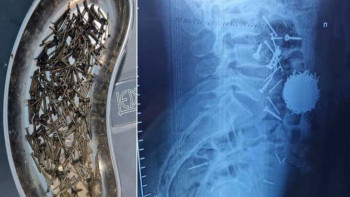

Өзбекстанда науқастың асқазанынан 200 грамм шеге шықты

Өзбекстанда науқастың асқазанынан 200 грамм шеге шықты Өзбекстанда дәрігерлер науқастың асқазанынан 200 грамм шеге алып шықты...